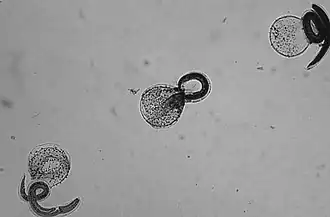

En Amérique du Nord, le taux d'infection des ratons laveurs par B. procyonis est très élevé : il est d'environ 70 % chez les adultes et de 90 % chez les jeunes[3]. La transmission se produit de façon semblable à celle des autres nématodes, par la voie fécale et orale. Les œufs sont produits par le ver dans l'intestin et, une fois excrétés, parviennent à un stade infectieux dans le sol. Lorsque l'œuf infectieux est ingéré, la larve éclot et entre dans l'intestin. La transmission de B. procyonis peut aussi se produire par l'ingestion de tissus infectés de larves[3].

Le ver adulte, ver allongé de 12 (mâle) à 23 (femelle) cm de long, effilé aux extrémités, qui ressemble beaucoup à l'ascaris du chien, vit et se reproduit dans l'intestin de son hôte définitif, le raton laveur[6]. La femelle peut pondre de 115 000 à 179 000 œufs par jour. Ils sont excrétés dans les matières fécales et deviennent infectieux dans le sol après deux à quatre semaines. S'ils sont ingérés par un autre raton laveur, le cycle de vie se répète ; mais s'ils le sont par un hôte intermédiaire (un petit mammifère ou un oiseau), les larves de B. procyonis percent la paroi intestinale et migrent dans les tissus de l'hôte. Elles ont tendance à migrer jusqu'au cerveau, causent des dommages et altèrent le comportement de l'hôte intermédiaire, ce qui en fait une proie plus facile pour le raton laveur. Le nématode ne se reproduit pas dans l'hôte intermédiaire (le chien a toutefois été reconnu pour être un porteur occasionnel de vers fertiles[5]), mais si le raton laveur fait sa proie de cet hôte, les larves enkystées peuvent alors atteindre le stade adulte, et le cycle reprend[2].